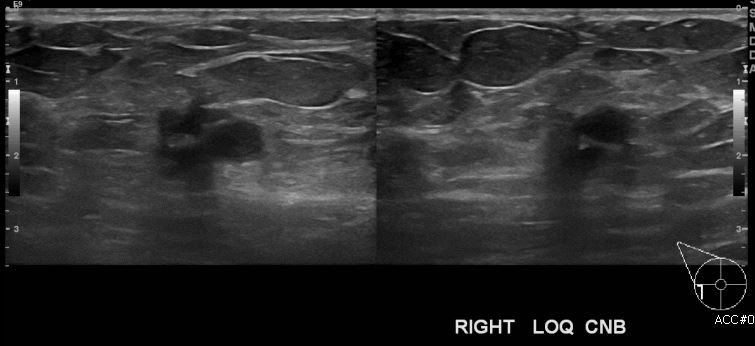

상기환자 건강검진상 이상소견으로 내원하신 60대 여성분으로 초음파상 우측유방

하외측 의심스러운 멍울 조직검사 시행하여 우측 침윤성 유관암 진단 되었습니다.